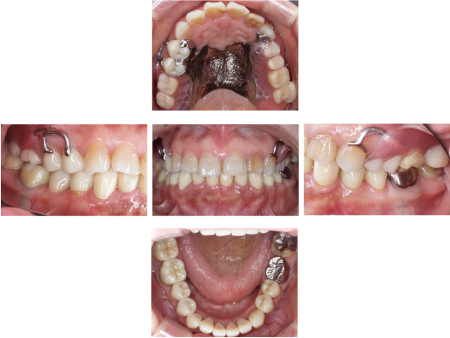

その後、下の被せ物治療を開始しました。最初に被せ物装着後のお口の中を再現するために模型を作製し、入れ歯を入れる高さが十分に確保され下の歯に当たらないことを確認後、下の歯12本(右下第2大臼歯〜左下第2小臼歯)に順次被せ物を作製・装着して噛み合わせの高さを上げていきました。

被せ物は自然な白さで耐久性もある「ジルコニアクラウン」を採用しています。

最後に上の部分入れ歯として、適合がよく装着時の違和感が少ない「金属床義歯」を作製し、治療を終了しました。